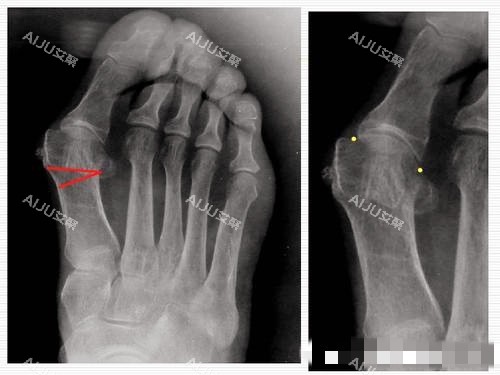

技术认证:掌握小创口拇外翻矫正、传统截骨术等多种术式,能根据患者脚型灵活调整;

中重度拇外翻:精密截骨+关节复位,解决骨头变形问题;

求美者王先生(45岁,重度拇外翻)反馈:“我这拇外翻十几年了,走路久了脚腕都疼,担心手术创伤大。李医生给我做的是精密截骨术,手术时间不到1小时,术后当天就能拄着拐慢慢走。本来以为要躺1个月,结果3周就不用拐了,现在3个月过去,穿正常鞋子完全没问题,也不疼了。”